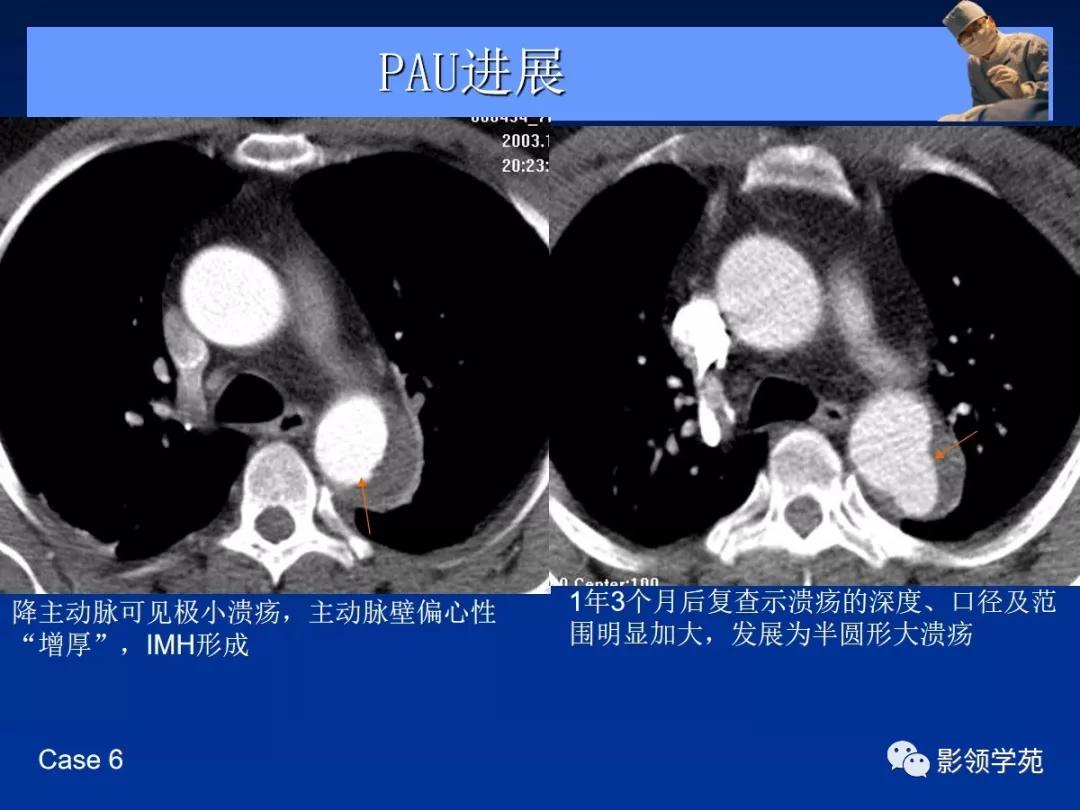

- 主动脉穿通性溃疡( penetrating aortic ulcer, PAU )